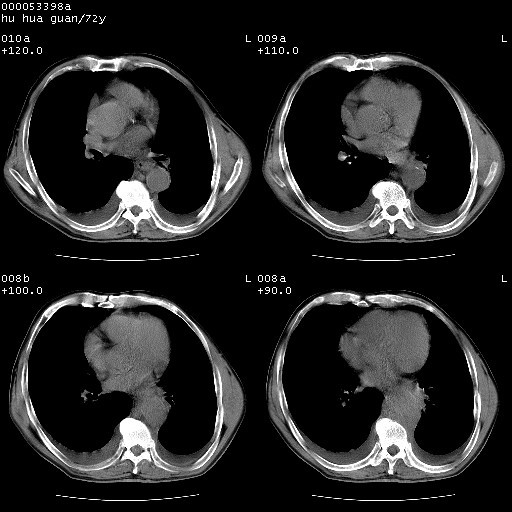

降主动脉前移位,后纵隔占位

后纵隔占位,降主动脉前移位;双侧胸腔积液;应排外食管病变侵犯血管可能;

可以明确的说。肯定不是主动脉夹层破裂出血!考虑为淋巴瘤或间叶组织来源的恶性肿瘤可能性大。右肺小结节建议薄层观察,如能发现恶性征象,那椎前改变就考虑为转移所致。至于双侧少量胸水乃静脉血回流受阻所致。

1、右上肺结节病变,肺泡癌不除外,请随诊;左下肺近后纵隔病变,考虑纵隔型肺癌侵犯大血管可能;

2、右下肺背段少许炎症,双侧胸腔积液,右下肺纤维索条。